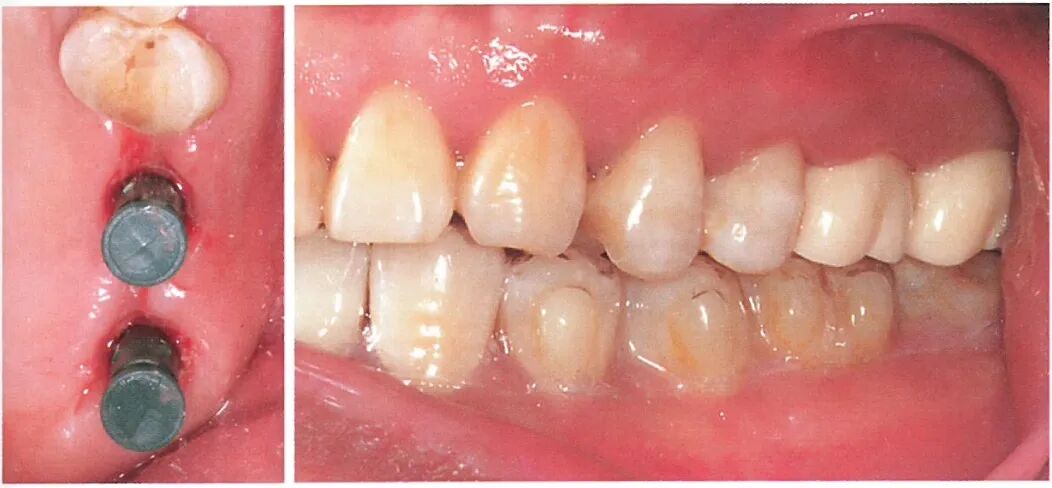

与患者沟通后,患者选择正畸方式压低对颌牙。我们在26、27 位点植入两颗植体后,患者开始接受隐形矫治配合橡皮圈同时压低36、37。通过正畸压低的方式,患者的36、37与术前相比被明显压低。

术后6个月行二期手术更换愈合基台,使用6.5mm 高的愈合基台检测发现修复距离足够。